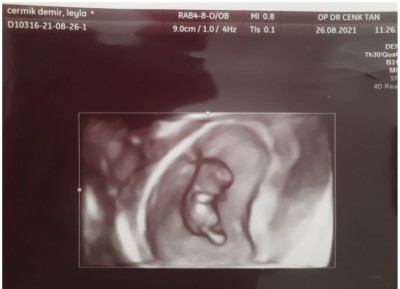

image

dburda tam 9 haftalikti net şekilde görülmeye başlıyor bbu haftada :))))

Hadi hayırlısı canım. Benm bebeğim burda 9hafta 3 gunluktu doktorumun 4d ultrasonu var. 12.haftada da

erkek oldugunu öğrendik  :)

Amin inşallah. Rica ederim canim. Seninki de böyle gorunur gittiginde merak etme siyah beyaz ekranda da kolu bacagi belliydi. Hele bide doktor 4d ekranı açınca gözlerim dolmuştu. Hareket bile ediyordu çok şaşırmıştım. :) inşallah bi an önce bebeklerimize sağlıklı kavuşuruz canım.